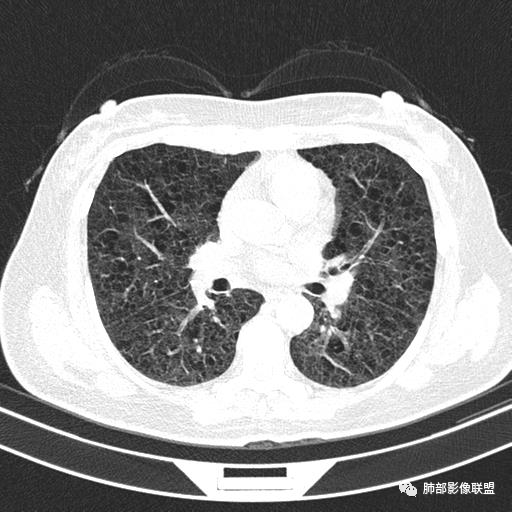

中年女性,不吸烟

双肺弥漫囊腔,累及肋膈角,囊腔形态相对规则单一。

CT平扫示双肺弥漫分布大小不等囊状薄壁透光区,无内、中、外带分布差异,间质稍示增厚。拟LAM

中年女性育龄期妇女,咳嗽气喘,无吸烟史,有苯吸入史。影像:双肺弥漫均匀小囊腔,无明显分布优势,囊腔形态欠规则,壁薄,部分囊腔边缘血管征,伴双肺弥漫磨玻璃影,无结节,考虑lam,鉴别苯中毒肺损伤,囊腔多有分布优势,小叶中心分布为主,形态规整等

女,46,活动性气喘1年。苯吸入史半年。胸部CT:两肺弥漫囊腔,上至肺尖,下至肋膈角,形态类似小囊腔。考虑:LAM,鉴别LIP,BHD,PLCH等。

CT表现:双肺弥漫大小不等的薄壁囊腔,囊壁<2mm,外形规则,血管影多位于囊腔周围,囊腔之间肺组织正常,随着疾病进展到晚期,囊腔变大、增多,不可胜数,囊腔可融合成较大的囊,与肺气肿相似,形成间质性肺纤维化。部分病例可出现结节影。